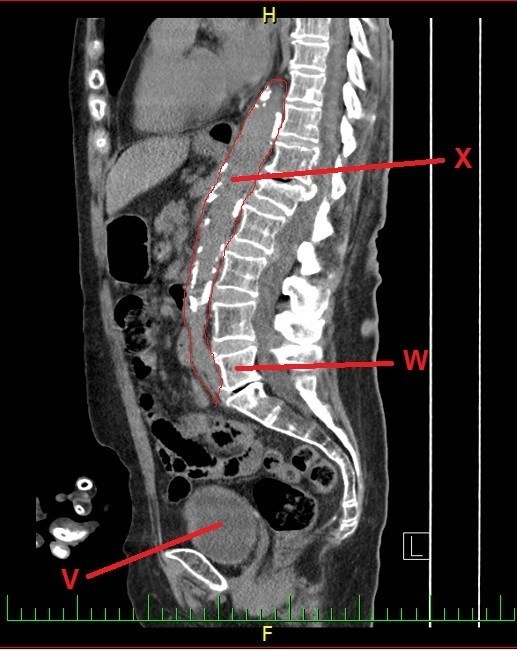

A dál co potřebujete k získání finálních souřadnic? Trocha z té zdravotnické praxe. Správný geokačer má silně vyvinutý smysl pro všímání si detailů, skrytých souvislostí a tak podobně. Princip je jednoduchý. Nepůjde o žádnou kdoví jak složitou matematickou šifru s IT podtextem. V budoucích několika minutách, hodinách či dnech se z Vás stanou radiologové (lékaři zabývající se zobrazovacími technikami) a anatomové. Tak Vás jistě nepřekvapí několik obrázků, na kterých bude vyznačen útvar, který musíte poznat a latinsky (pokud jiným jazykem, tak Vás na to upozorním) pojmenovat. Myslím, že vše bude jasné. Tak jdeme na to…

V - počet písmen v názvu útvaru (latinsky, 2 slova)

W - číselné označení pořadí (pozor, pouze v daném oddílu)

X - počet písmen v názvu útvaru (latinsky, 1 slovo)